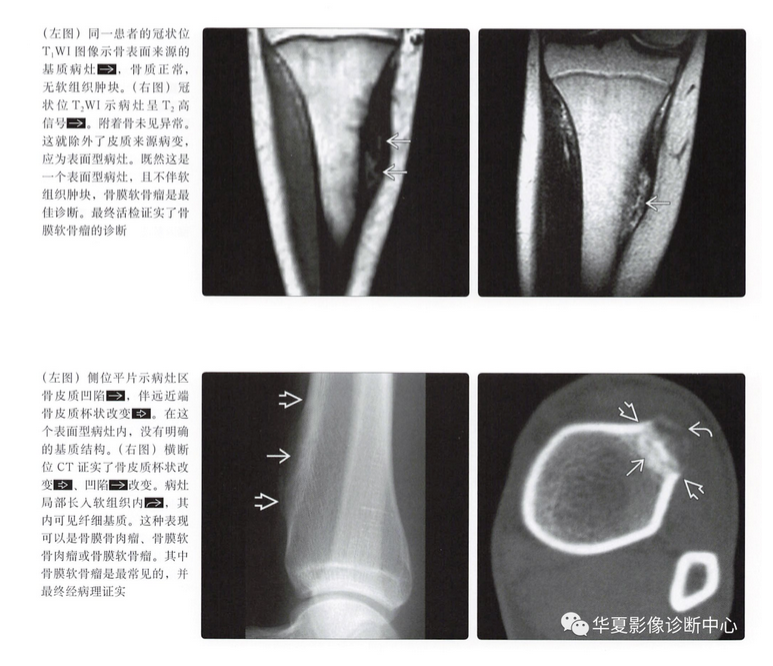

平片表现

- 骨皮质扇形凹陷

- 硬化边

- 致密性骨膜反应,尤其是在病灶近端、远端

- 病灶远端、近端骨皮质杯状改变

- 基质钙化(75%)

CT表现

- 与平片表现类似

- 可以更好地显示软骨基质和扇形凹陷

骨膜软骨肉瘤

骨膜骨肉瘤

- 中度恶性的表面型骨肉瘤

- 与骨膜软骨瘤发病部位相同

- 与骨膜软骨瘤几乎有相同的平片表现

- 附着骨皮质有相似的扇形塌陷倾向

- 常可见到基质钙化

- 骨样特点有时难以与软骨鉴别